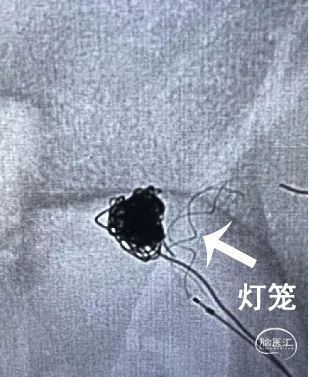

支架释放至瘤颈口处推灯笼

如果需要应用灯笼技术,支架释放至瘤颈口处保持微导管张力,推送支架予释放。